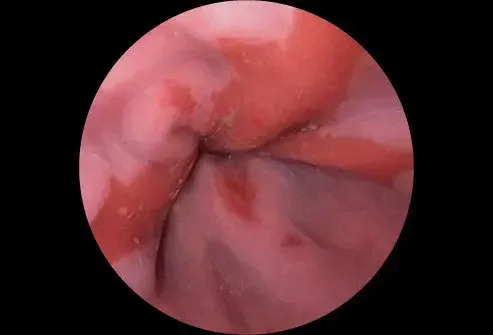

Le sphincter œsophagien inférieur

Lorsque vous avalez de la nourriture, il parcourt l'œsophage et passe à travers un anneau musclé connu sous le nom de sphincter œsophagien inférieur (LES). Cette structure s'ouvre pour permettre aux aliments de passer dans l'estomac. Il est censé rester fermé pour maintenir le contenu de l'estomac où ils appartiennent. Si la valve est faible ou endommagée d'une manière ou d'une autre, elle peut s'ouvrir et permettre au contenu de l'estomac et à l'acide de revenir ou de reflux dans l'œsophage. Le reflux acide produit une sensation de brûlure.